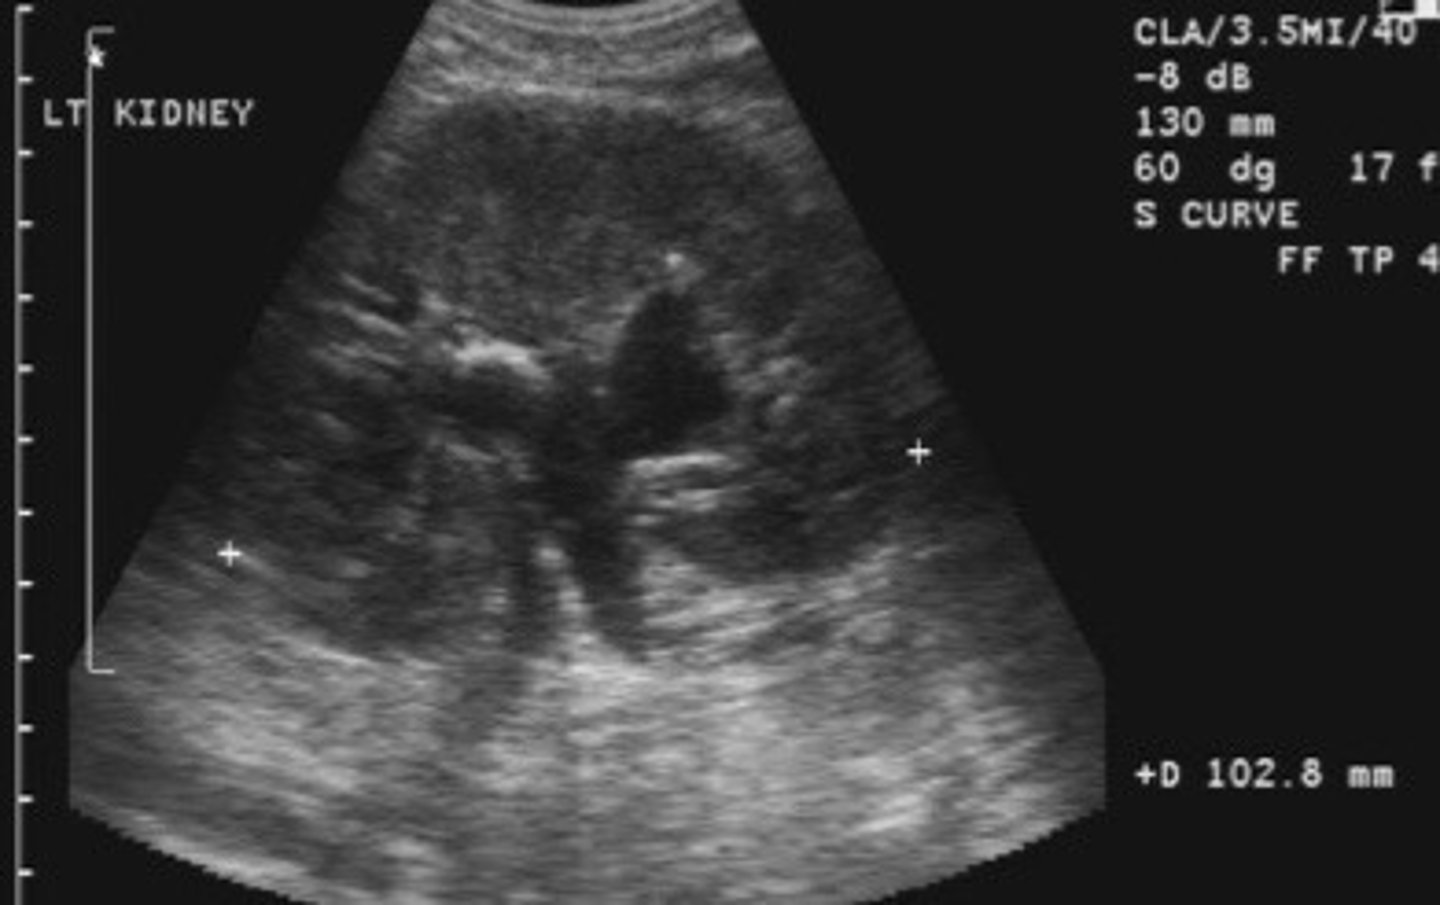

Grade 1 hydro

What does this image show